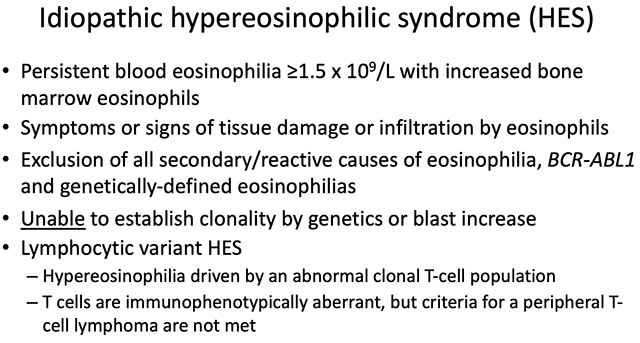

Idiopathic Hypereosinophilic Syndrome (IHES)

_____________________________________

• Diagnosis of exclusion

– All reactive/secondary causes of hypereosinophilia

– Lymphocyte-variant of HES

– CEL, NOS

– WHO-defined myeloid malignancies (eg, AML, MPN)

– WHO-defined MLNE with eosinophilia with PDGFRA, PDGFRB, FGFR1 and PCM1-JAK2

__________________________________________

Px:

Generally does better than CEL

Hypercellular bone marrow with panhyperplasia; All ancillary studies are negative... Diagnosis? = Idiopathic hypereosinophilic syndrome (IHES)